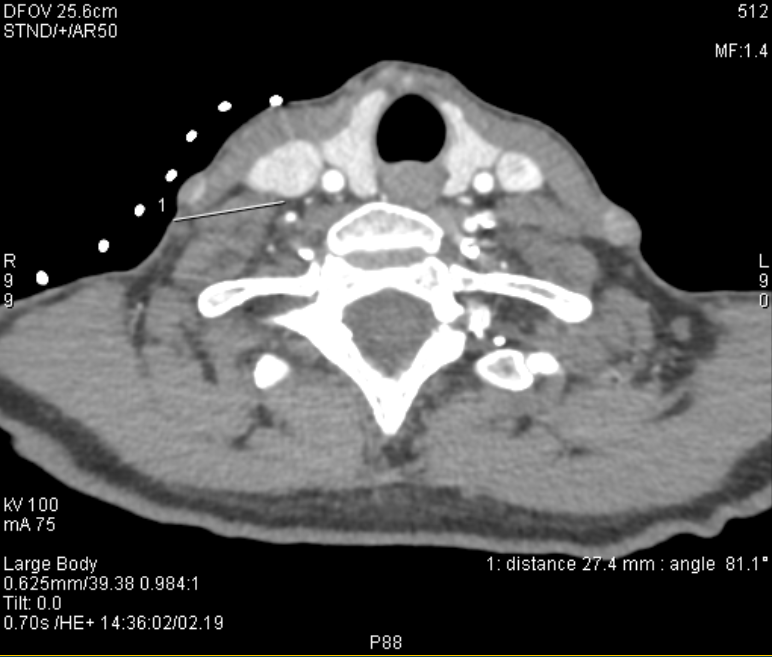

Advanced Nerve Blocks

Using high precision ultrasound and CT guidance, our experts are able to block deep nerves throughout the body. These are often performed as a test to determine which nerves are responsible for pain. Once a site is identified, it is targeted for further treatment using one of the more long lasting techniques. Targets include the coeliac plexus, stellate ganglion, lumbar sympathetic plexus, trigeminal nerve and others.